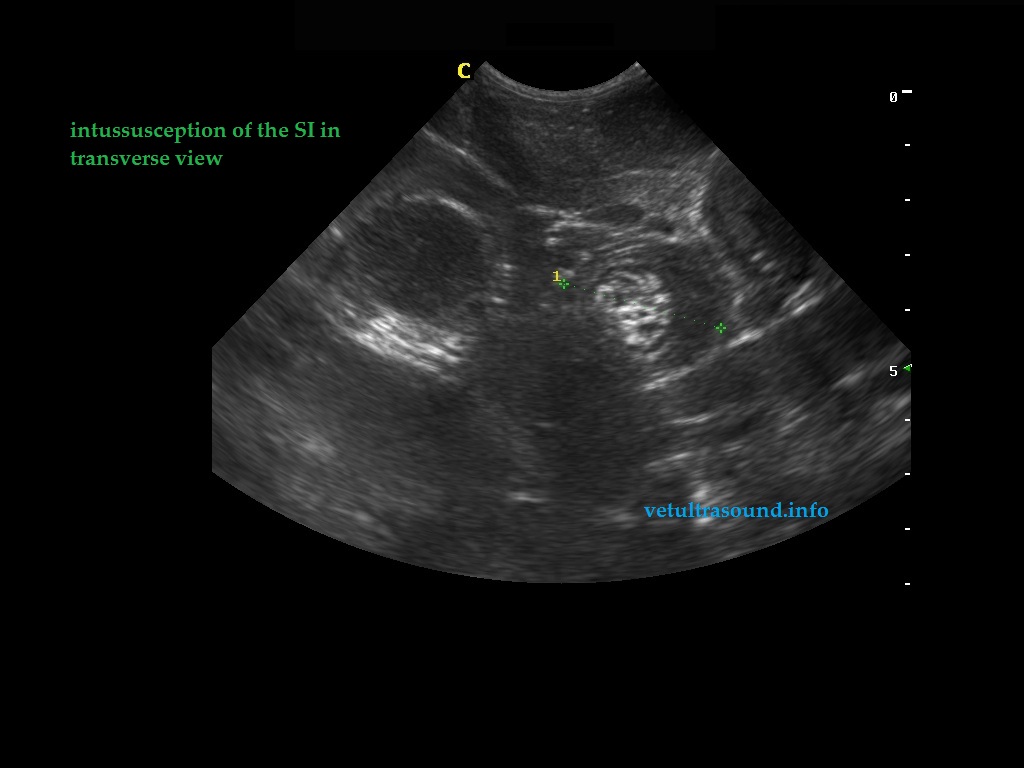

Findings: Distention of large part of the small intestine, caused by intussusception. The blood flow in the mesenteric arteries which supplied the intussusception was normal. The mesenteric lymphnodes were enlarged. A small amount of ascistic fluid was noted.

Ευρήματα: Στον υπερηχοτομογραφικό έλεγχο της κοιλίας βρέθηκε παρουσία εγκολεασμού σε τμήμα του λεπτού εντέρου. Η αιμάτωση των μεσεντέριων αγγείων του εγκολεσθέντος τμήματος εκτιμήθηκε φυσιολογική. Οι μεσεντέριοι λεμφαδένες βρέθηκαν διογκωμένοι με αντιδραστική ηχομορφολογία. Υπήρχε μικρή ποσότητα ασκιτικού υγρού. Οι υπόλοιπες εντερικές έλικες που αφορούσαν το τμήμα του λεπτού εντέρου πριν τον εγκολεασμό βρέθηκαν διατεταμένες .